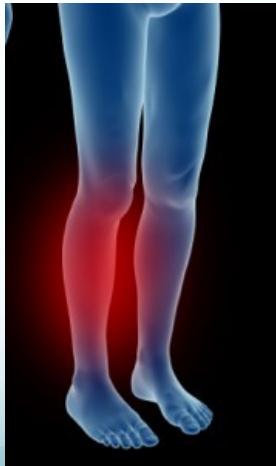

Growing Pains

- Diagnosis: By exclusion of all other diseases

- Location: Pain in legs, not at joints

- Age groups: 3-5 years and 8-12 years

- Diagnostic criteria (MUST meet all 3):

- Bilateral leg pain

- Pain occurs only at night

- No limping nor pain symptoms during the day

Clinical Examples:

(Source: KidsHealth.org)